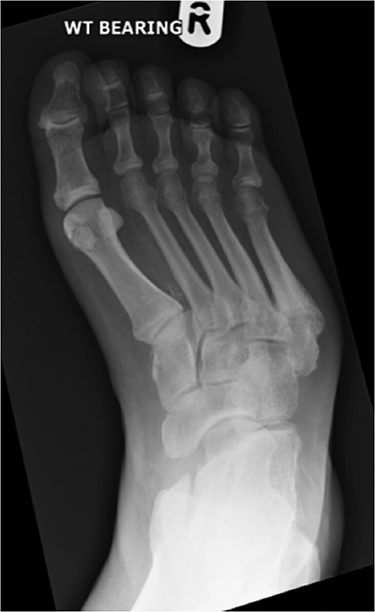

A 62-year-old male with a 22-year history of insulin-dependent diabetes and associated neuropathy and retinopathy presented following a fall. He sustained a fifth metatarsal base fracture of his right foot with resultant de-functioning of the peroneus brevis. This led to progressive varus of the forefoot, with subsequent midfoot collapse as a result of Charcot neuroarthropathy (Figs 1 and 2).

Anterior–posterior radiograph of right foot demonstrating fracture at base of fifth metatarsal and forefoot varus.